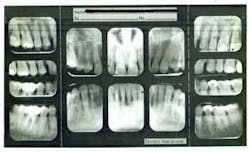

Figures 2a and 2b: Initial presentation in 2011 of the upper right and left molar area, showing advanced bone loss with furcation involvement on the molars.

At presentation, Martin was in his fifties with a medical history significant for controlled hypertension with no known food or drug allergies. He had been lackadaisical with his dental care in the past because of his busy schedule, but he was motivated to get his hygiene and treatment under control. He denied a history of smoking/alcohol/drug use. Based on his full-mouth series (figure 1) and clinical presentation, Martin had generalized, moderate bone loss with localized, severe bone loss in the posterior maxillary right and left quadrants (figures 2a and 2b) as well as the mandibular anterior incisor area (figure 3).